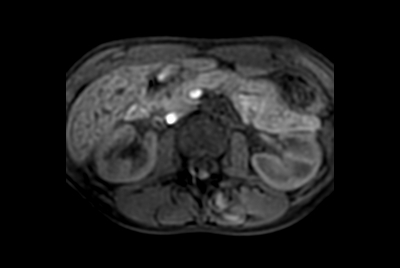

Multi-phase, contrast-enhanced renal imaging